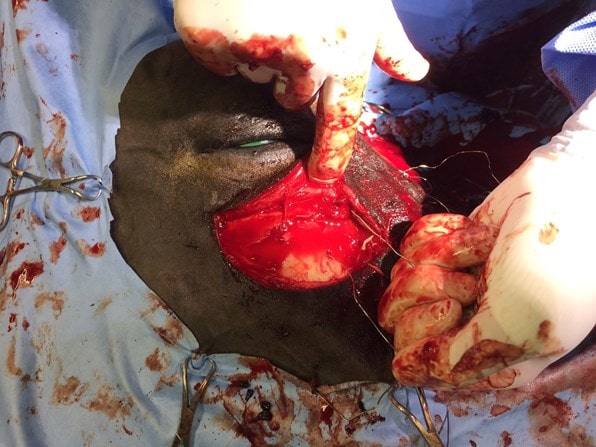

An initial attempt was made to elevate the dorsal and ventral fragments using elevators and Steinman pins through stab incisions. It became clear that this would not produce the leverage required and so two semi-circular incisions were made dorsally and ventrally but not connected to preserve the nasolacrimal duct (assuming it had not already been severed by a bone fragment). Exposure of the fracture showed that there were at least eight large fragments with several smaller pieces of loose bone being discarded.

Some fragments were depressed to the extent that they were coursing vertically into the head, perpendicular to their normal position. The fractures extended around the dorsal margin of the orbit. The fragments were gradually levered back into their normal position but it also was clear that they would not be self-retaining and so adjacent fragments were secured to one another using stainless steel wire. One large central loose fragment was obscured by the tissue between the two incisions and so the incisions were connected rostrally.